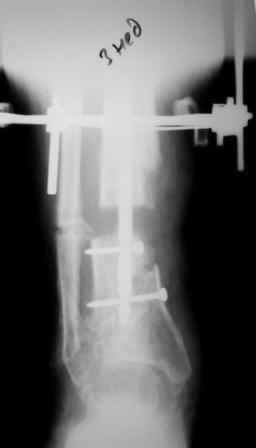

Коллеги!Позвольте продолжить обсуждение темы «ложный сустав левой голени.» Больной К 45 лет, начало см. http://www.weborto.net/forum/1228422607/ И рассказать о результатах проделанной работы. Остановились на следующей тактике 1) Наложить Аппарат Илизарова. В аппарате восстановить оси трех смещенных относительно друг-друга фрагментов большеберцовой кости. Устранить вальгусную деформацию дистального отдела большеберцовой кости. Что и было выполнено. - Была выполнена репозиция в аппарате (рис1) 2) После репозиции более очевидна стала проблема дефекта кости в верхней трети голени, два фрагмента свободно лежат. Остановились на варианте перехода на интрамедуллярный синтез стержнем с покрытием костный цемент+ванкомимцин и замещении дефекта с помощью транспорта фрагмента (рис 2) 3) Третьим этапом наложили модуль на промежуточный фрагмент.(рис 3) И начали его транспорт на стержне в проксимальном направлении. (рис 3 а) Надеемся что «вырастет» регенерат в дистальном отделе, а в проксимальном отделе фрагмент «упрется» и прирастет. Хочу сказать слова благодарности за обсуждение на форуме этого случая. Особые слова благодарности Иванову Павлу Анатольевичу!!! Он помогал Словом, а самое главное делом. Приезжал, оперировал! За что ему нижайший поклон! С ув Коробушкин Г

Да, это единственное, что "царапает глаз" при разглядывании этой интересной серии снимков.

Мы сейчас обычно вводим отклоняющую спицу еще пока голень лежит на столе горизонтально, до сгибания в колене для формирования канала и т.п.

Для восстановления оси "по-правильному" надо извлечь гвоздь, ввести отклоняющий винт или спицу, и ввести гвоздь повторно. А пытаться

исправить ось с гвоздем внутри мэтрами, например, проф. Шнеттлером, не рекомендуется. Мы, однако, попробовали - получается. Надо убрать запирающие винты из центрального отломка. В данном случае, при наличии не перелома, а дистракционного диастаза, надо использовать дистрактор. С помощью спиц которого, введенных с гиперкоррекцией, ось и исправить. Раз канал там широкий, получиться должно легко. После чего ввести винт кнаружи от гвоздя, а потом и винты через гвоздь.